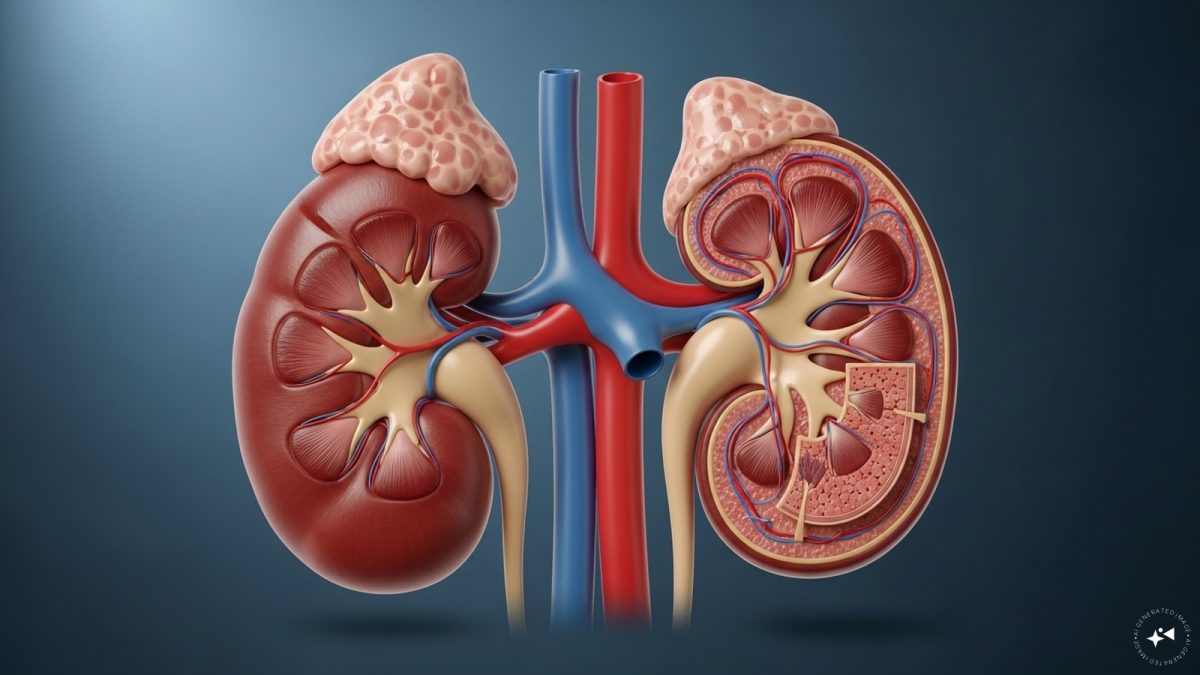

Your kidneys quietly filter blood and remove waste every day. When they struggle, the warning signs are often subtle—catching them early is key.

Unexplained Swelling: Puffiness around ankles, feet, or face may signal kidneys leaking protein. Without enough protein in the blood, fluids build up in tissues.

Foamy or Bubbly Urine: Persistent frothy urine can mean excess protein (proteinuria) is being lost. It’s an early red flag that kidney filters are breaking down.

Sudden Weight Gain: A quick rise on the scale without lifestyle changes could be fluid retention. This “heavy” weight often comes with swelling and sluggishness.

Persistent Fatigue: Protein loss and toxin build-up reduce energy levels. This isn’t normal tiredness—it’s deep exhaustion that doesn’t improve with rest.

Appetite Loss & Nausea: As kidneys fail to filter properly, toxins accumulate. This makes food less appealing, sometimes triggering nausea or vomiting.

Frequent Nighttime Urination: A strong urge to urinate at night (nocturia) signals kidneys struggling to balance fluids. It disrupts sleep and points to early strain.

Frequent Infections: Weakened immunity from protein loss leaves the body prone to UTIs and respiratory infections that take longer to heal.

Chronic kidney disease affects 10% of the global population. If you notice these signs, consult a doctor early.